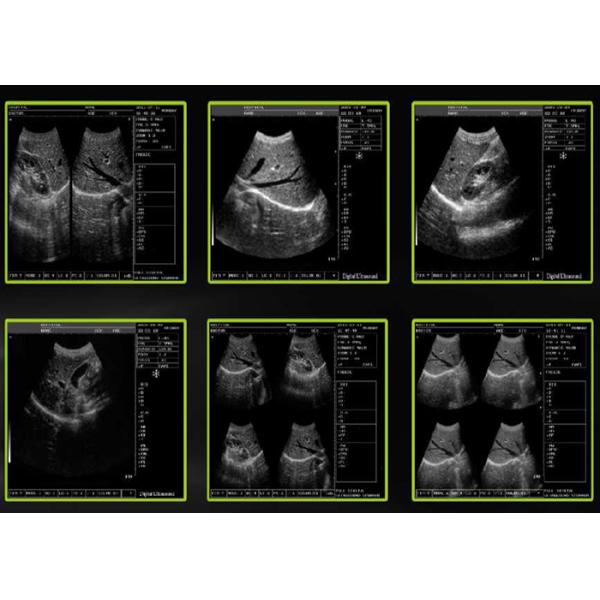

10 inch CRT Monitor Black White Ultrasound Machines Portable Ultrasound Scanner

10 inch CRT Monitor Black White Ultrasound Machines Portable Ultrasound Scanner Images |